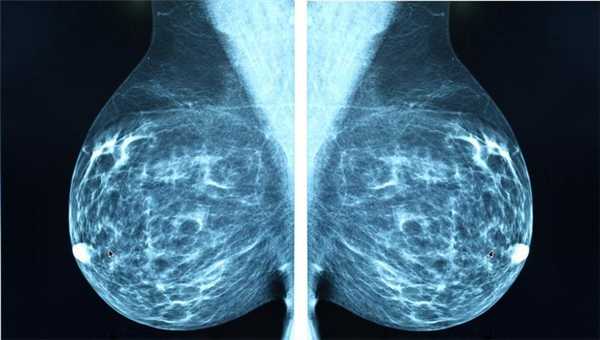

Маммография

Отдельный вид рентгенографии, разработанный для диагностики заболеваний молочной железы, поэтому проходят маммографию женщины. О рекомендуемом возрасте для проведения процедуры единого мнения нет. Маммография помогает убедиться в отсутствии злокачественной опухоли с точностью до 89%. Считается, что женщины должны проходить обследования регулярно, начиная с 39 лет, хотя некоторые онкологические сообщества рекомендуют обследоваться с более молодого возраста.

Маммографию назначают для диагностики рака молочной железы, процедура проходит быстро, это плюс, но пациентку облучают, а риск неверного диагноза остаётся, это минус. Маммография может быть цифровой и плёночной, цифровая маммография обеспечивает получение более чёткого снимка.

Классический рентген по-прежнему остаётся важным методом для диагностики самых разных заболеваний. Например, маммография (рентгеновское исследование молочных желез) - лучший способ скрининга рака молочной железы. Возможности КТ в выявлении злокачественных и воспалительных процессов в этом органе существенно ниже.